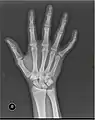

Left hand shown with thumb on left.

The metacarpals form a transverse arch to which the rigid row of distal carpal bones are fixed. The peripheral metacarpals (those of the thumb and little finger) form the sides of the cup of the palmar gutter and as they are brought together they deepen this concavity. The index metacarpal is the most firmly fixed, while the thumb metacarpal articulates with the trapezium and acts independently from the others. The middle metacarpals are tightly united to the carpus by intrinsic interlocking bone elements at their bases. The ring metacarpal is somewhat more mobile while the fifth metacarpal is semi-independent.[1]